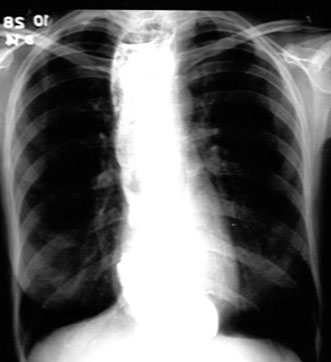

Esophagram of a patient with achalasia. Note the extent of dilated esophagus